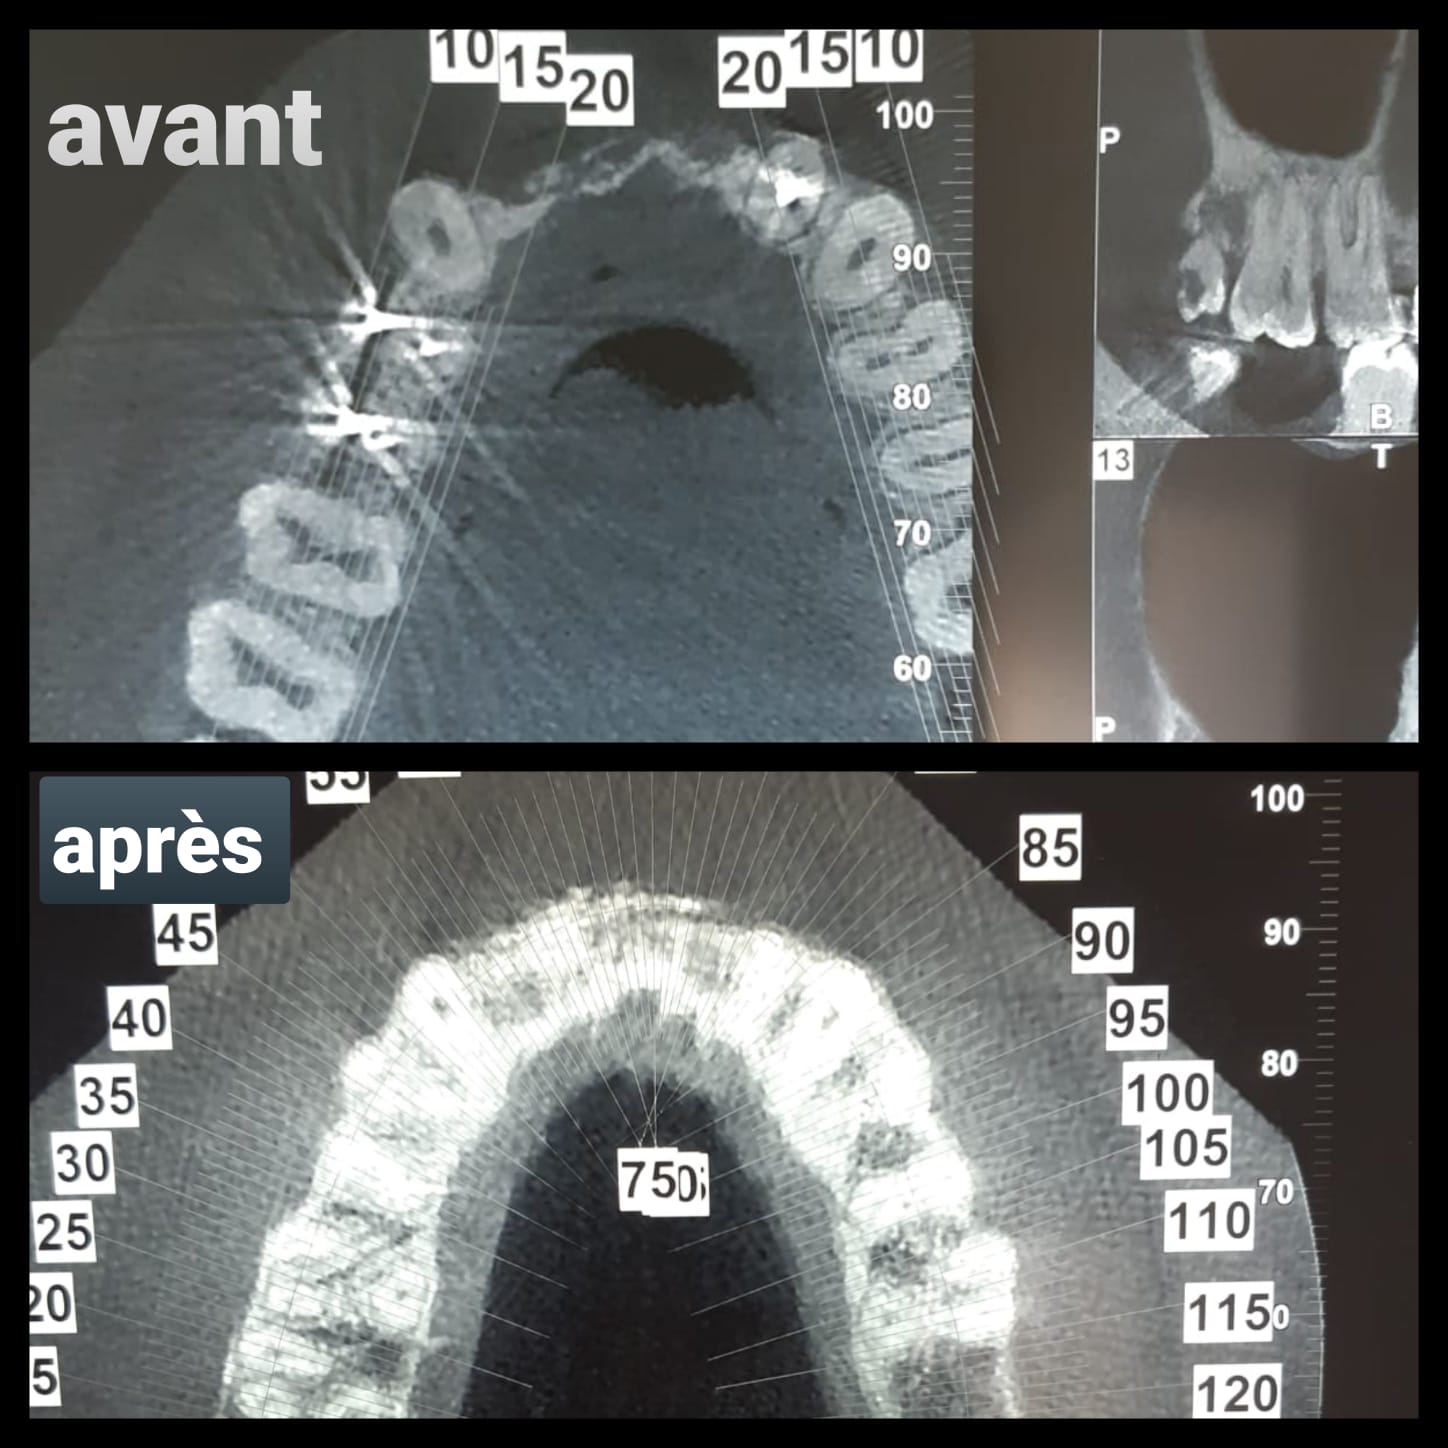

Voici un cas de grosse résorption antérieure que j'ai greffé Aout 2020

Le Scan de décembre soit 4 mois post Op montre un bon épaisissement du volume de crête par contre en Vestibulaire de 12 une coaptation pas très adhérente ...apparemment ..

Je dois poser 2 implants en 12 et 21 pour faire un bridge 3 eléments 12/21.

Faudra t il regreffer en vestibulaire ?..risque de spire apparente .(je dois poser 2 Implants de diamètre 3.75 par 13)

Et en plus présence du canal incisif palatin qui va être très proche de 21